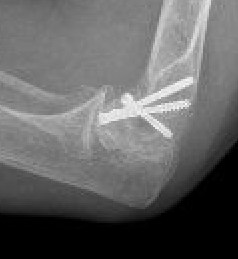

Lateral approach and ORIF

Technique

Arm on side table with tourniquet

- lateral approach centered on lateral epicondyle

- split extensor muscle

- open capsule and identify capitellum fracture

- reduce fracture

Usually AP headless compression screws (violates articular surface)

- +/- PA screws (risk AVN)

- +/- excise isolated cartilage lesions

- +/- postero-lateral plate

ORIF with AP screws